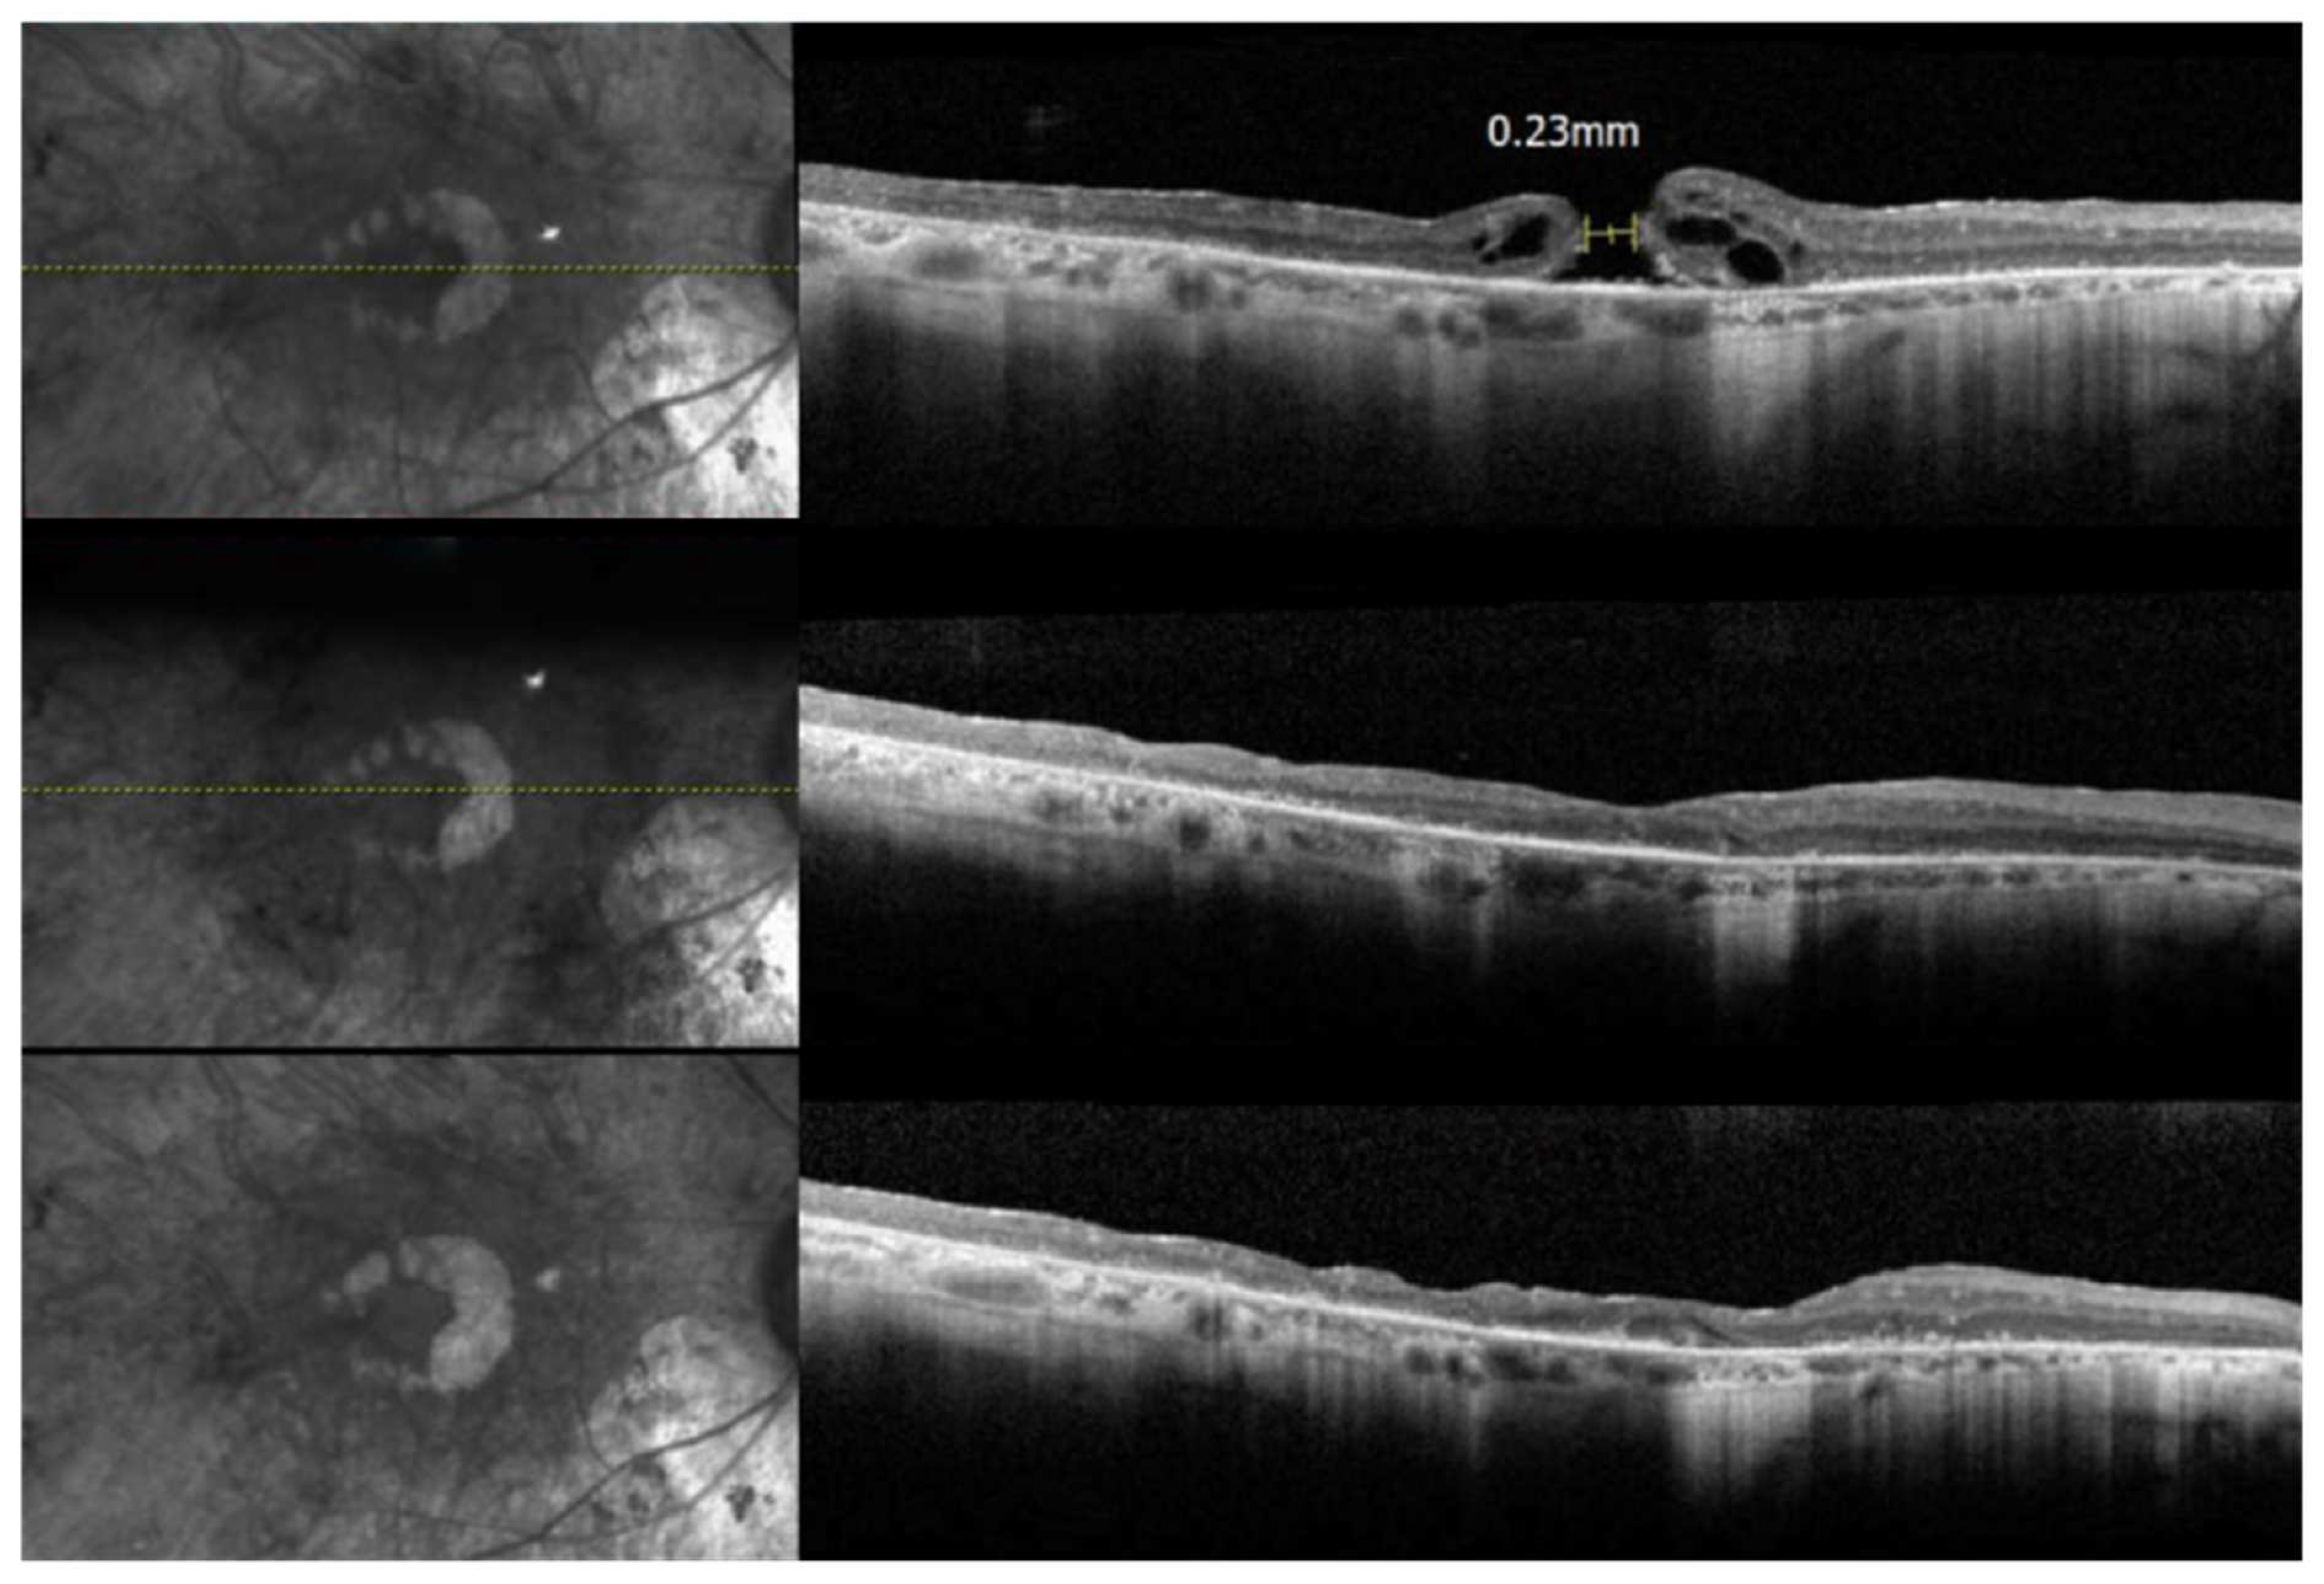

3.3. An Isolated Case of Full Thickness Macular Hole Leading to Rapid Vision Loss with Successful Repair

| P7 | F3 | F | 70 | 20 s | 16 Years | Nephrolithiasis, Hypertension, Hyperlipidemia | PCIOL OU, Hx of PSC OU, CME OU, ERM OU, FTMH OD, PTMH OS | c.2431C>T | 20/60 | 20/40 | GVF of less than 10 degrees OU. Smallest target seen is V4e. |